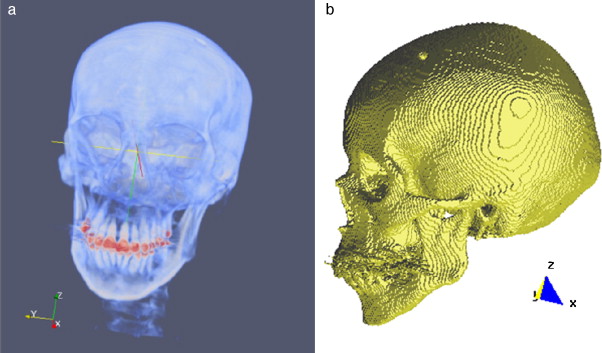

El modelo geométrico del cráneo obtenido con la metodología es presentado en la figura 23 . Las vistas presentadas en la figura han sido generadas empleando ParaView.

|

|

|

Figura 23. Vistas volumétrica del modelo del cráneo. (a) Vista del volumen original en ParaView. (b) Vista de la superficie del cráneo en GiD. |